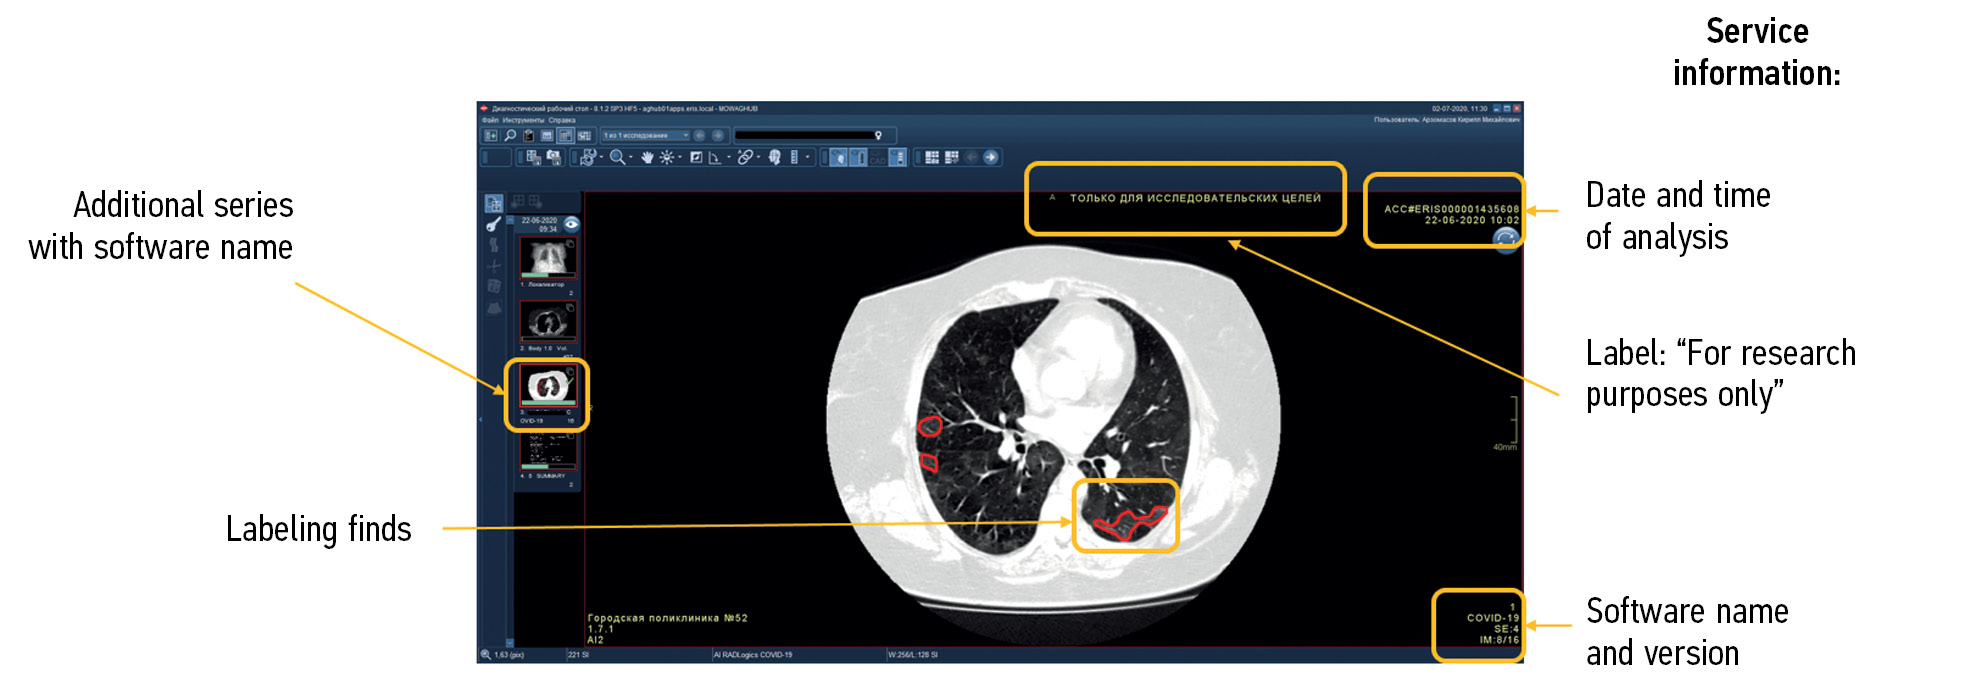

Functional testing is a stage wherein software functions specified by a supplier are checked for availability and functionality. This testing is performed at the technical and clinical levels. On a technical level, the software is assessed based on the following criteria: prioritization of research (triage), availability of an additional series of images from the software, presence of the other series’ name, presence of a graphical designation of software on the images of the different series, presence of a warning label “For research purposes only” on images and in DICOM SR, possibility of series synchronization, displaying the probability of abnormality, indication of the category of abnormality, and availability of complete DICOM SR protocol structure (Figures 2 and 3).

Fig. 2. Main components of the result of using artificial intelligence–based software with images: A reference example.